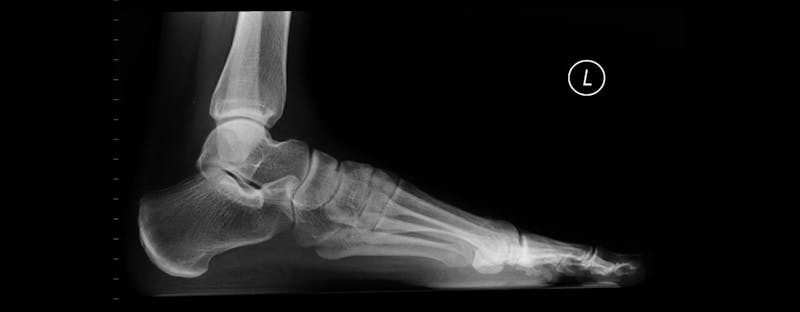

If you have flat fleet, you are not alone. Flat feet are defined by flattened foot arches that cause your soles to entirely touch the floor when you are standing. This podiatric condition is very common and often painless, which is why patients often avoid discussing the issue with their doctor. However, any pain or swelling in your feet should be reported to an experienced foot doctor.